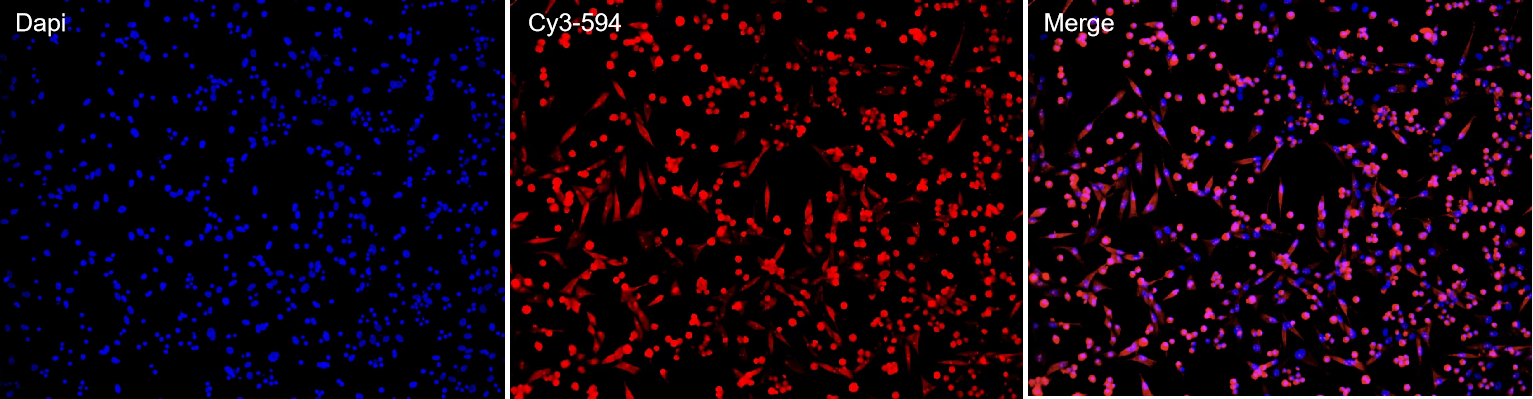

IHC/IF/ICC |

组织/细胞样本、抗体 |

染色图像+报告 |

1–2周 |

案例展示

抗体在肿瘤组织中显示出明确的特异性染色信号,定位清晰。